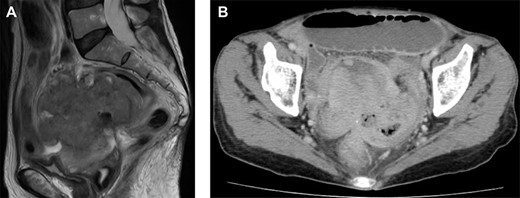

Magnetic resonance imaging and computed tomography (CT) findings preoperatively. (A) Sagittal T2-weighted MRI scan demonstrating a pelvic mass involving the uterus and rectum. (B) CT scan showing expansion of the intestines and the absence of free intraperitoneal air.

A 67-year-old postmenopausal woman, gravida 0, presented with purulent discharge and abdominal distension. Her past medical, surgical, gynecological and family histories were all unremarkable. The vaginal examination showed a foul smelling, green vaginal discharge and no tenderness of the uterus. Vaginal swab cultures grew Escherichia coli. The endometrial Papanicolaou test was negative. Laboratory results, including the blood count, differential, liver function and renal function, were within the normal range. There was no fever, weight loss or palpable lymphadenopathy and organomegaly. The transvaginal ultrasound image showed the presence of hypoechoic fluid in the uterine cavity, compatible with a diagnosis of pyometra (Fig. 1). Drainage of the purulent contents by uterine Foley catheter insertion was performed. The culture of the pus grew Klebsiella pneumoniae and E. coli. After draining the fluid, her symptoms disappeared temporarily. However, 3 months later, she was admitted to our hospital with abdominal pain that gradually worsened. On physical examination, her abdomen was very tender and showed diffuse peritoneal signs. Her vital signs were stable, but laboratory studies detected a mild increase in the levels of leukocytes (9510/μl) and C-reactive protein (1.24 mg/dl). The carcinoembryonic antigen (CEA) level was significantly increased (10.2 U/ml), and the cancer antigen-125 level was slightly increased at 102.7 U/ml. The magnetic resonance imaging scan demonstrated a pelvic mass involving

the uterus and rectum (Fig. 2A). The computed tomography scan showed expansion of the intestines and no evidence of free intraperitoneal air (Fig. 2B). As she had a history of bloody stool and the CEA level was increased, we performed colonoscopy, which showed a malignant tumor of the rectum (Fig. 3). The protruding tumor was located 7 cm from the anus. Exploratory laparotomy showed a 90-mm pelvic mass involving the uterus, ileum and rectum. Therefore, we performed an en bloc resection of the mass, including total hysterectomy, bilateral salpingo-oophorectomy, partial resection of the ileum and the Hartmann operation. Macroscopically, the resected pelvic mass invaded the uterus, intestine and rectum, and a colouterine fistula was identified (Fig. 4). The main portion of the tumor was located in the rectum, and it grossly appeared that tumor invasion occurred from the rectum to the uterus and ileum. Microscopic examination of the pelvic mass showed complicated glandular structures in a desmoplastic stroma. The cells forming the lumen were primarily columnar epithelium, consistency of the small glandular cavity was high and severe dyskaryotic cells were multilayered. The nuclei were enlarged and irregularly shaped, contained coarse chromatin and showed atypia. Immunohistochemical staining was performed. Cytokeratin (CK)20 (Dako), NCL-Villin (Novocastra) and CEA (Dako) were positive, and CK7 (Dako) was negative. The final diagnosis was moderately differentiated tubular adenocarcinoma of the rectum, stage IIC, pT4b N0 M0. The patient’s postoperative course was uneventful. The serum level of CEA returned within normal range 1 month postoperatively. Adjuvant chemotherapy (TS-1) was administered for 6 months postoperatively. The patient has been followed up with for >12 months without any signs of recurrence.